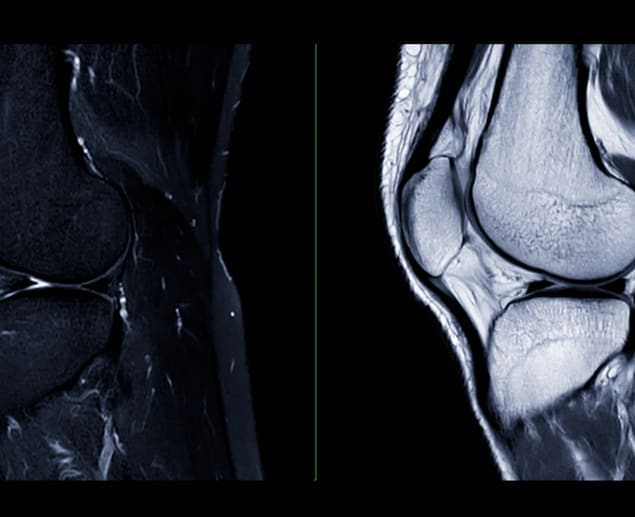

What Does an ACL Tear Look Like on MRI?

How your ACL tear will look on MRI depends on the timing of your scan and whether it’s a complete or partial tear, but your clinician will look for key signs of each on your MRI results.

The ACL may appear as a bright spot, which is a sign that it’s damaged or inflamed. A complete tear will often show as a gap or ‘space’ in the ligament, and the gap may look wavy.

Swelling and bleeding can create a cloudy appearance on your scan results, sometimes making it difficult to see all the details. Your clinician will look for broken or disconnected ACL fibres to confirm a tear. They may also look for evidence that the ACL is in a position different from usual. For example, if the angle of the ACL has changed by around 15 degrees or more, this suggests it is torn or pulling away from the shinbone or the point where it is attached (tibial insertion).

If the ACL looks bright on certain MRI images and the angle is normal, it’s more likely to be a partial tear rather than a complete one. Unlike a complete tear, where there is a clear gap in the ACL, a partial tear may still show a connection of the ligament fibres, although they may appear thinner or irregular. The shape of the ACL may also look wavy or irregular in form instead of straight and smooth. This can be a sign of damage.

Clinicians will also look for other structural issues or indirect signs that could indicate a torn ACL. For example, anterior tibial translation (ATT) - an abnormal space between the tibia and femur that is common in the case of a complete tear (ACL rupture), or a notch in the lateral femoral condyle which can be caused by the same internal rotation of the knee that can tear the ACL. In fact, the movement and instability of a torn ACL can also cause other tears, such as the posterior horn of the medial meniscus.

MRI Scan

Your doctor will recommend an MRI to provide detailed images of the soft tissues and ligaments around the knee areas, looking for primary and secondary signs of ACL injury. This will help them get a closer look at the injury and check for any associated damage, such as a meniscus tear.

ACL tear MRI scans use strong magnetic fields and radio waves to produce detailed images of the knee, allowing for the detection of any injuries to the anterior cruciate ligament (ACL).

The process begins by aligning the water molecules in the knee using magnets. Radio waves then momentarily disrupt this alignment, and as the molecules return to their original positions, they emit signals that the MRI machine captures.

A computer processes these signals to create detailed, slice-by-slice images, highlighting any areas of damage to the ACL or surrounding structures, such as swelling or tears.